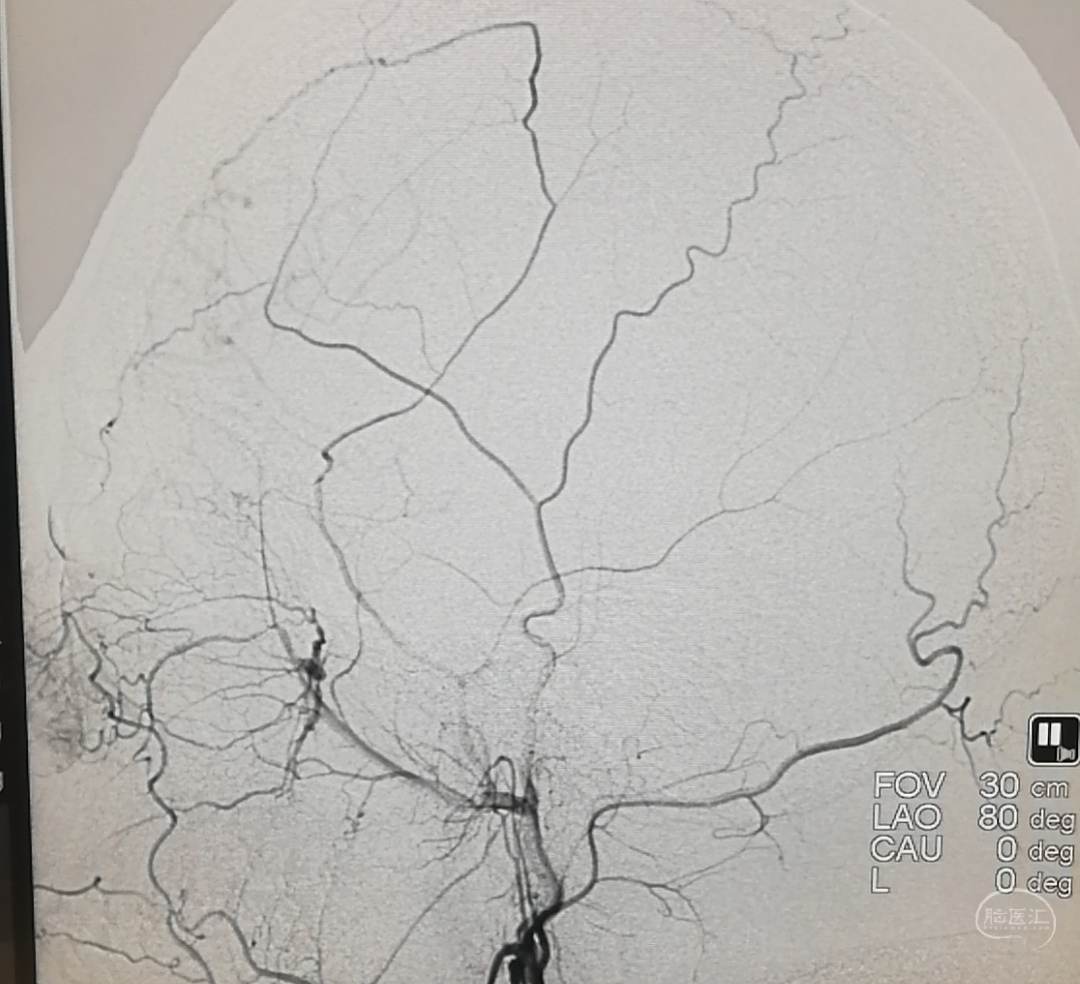

DSA示:左侧大脑前、大脑中动脉闭塞,烟雾样血管形成。

DSA示颞浅A未向颅内代偿。